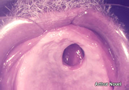

Su manifestación oral es una ulcera en el paladar (GOMA) y tarda meses en cicatrizar. También puede haber una esclerosis sifilica en el dorso de la lengua acompañada de una leucoplasia (lesión potencialmente maligna)

|